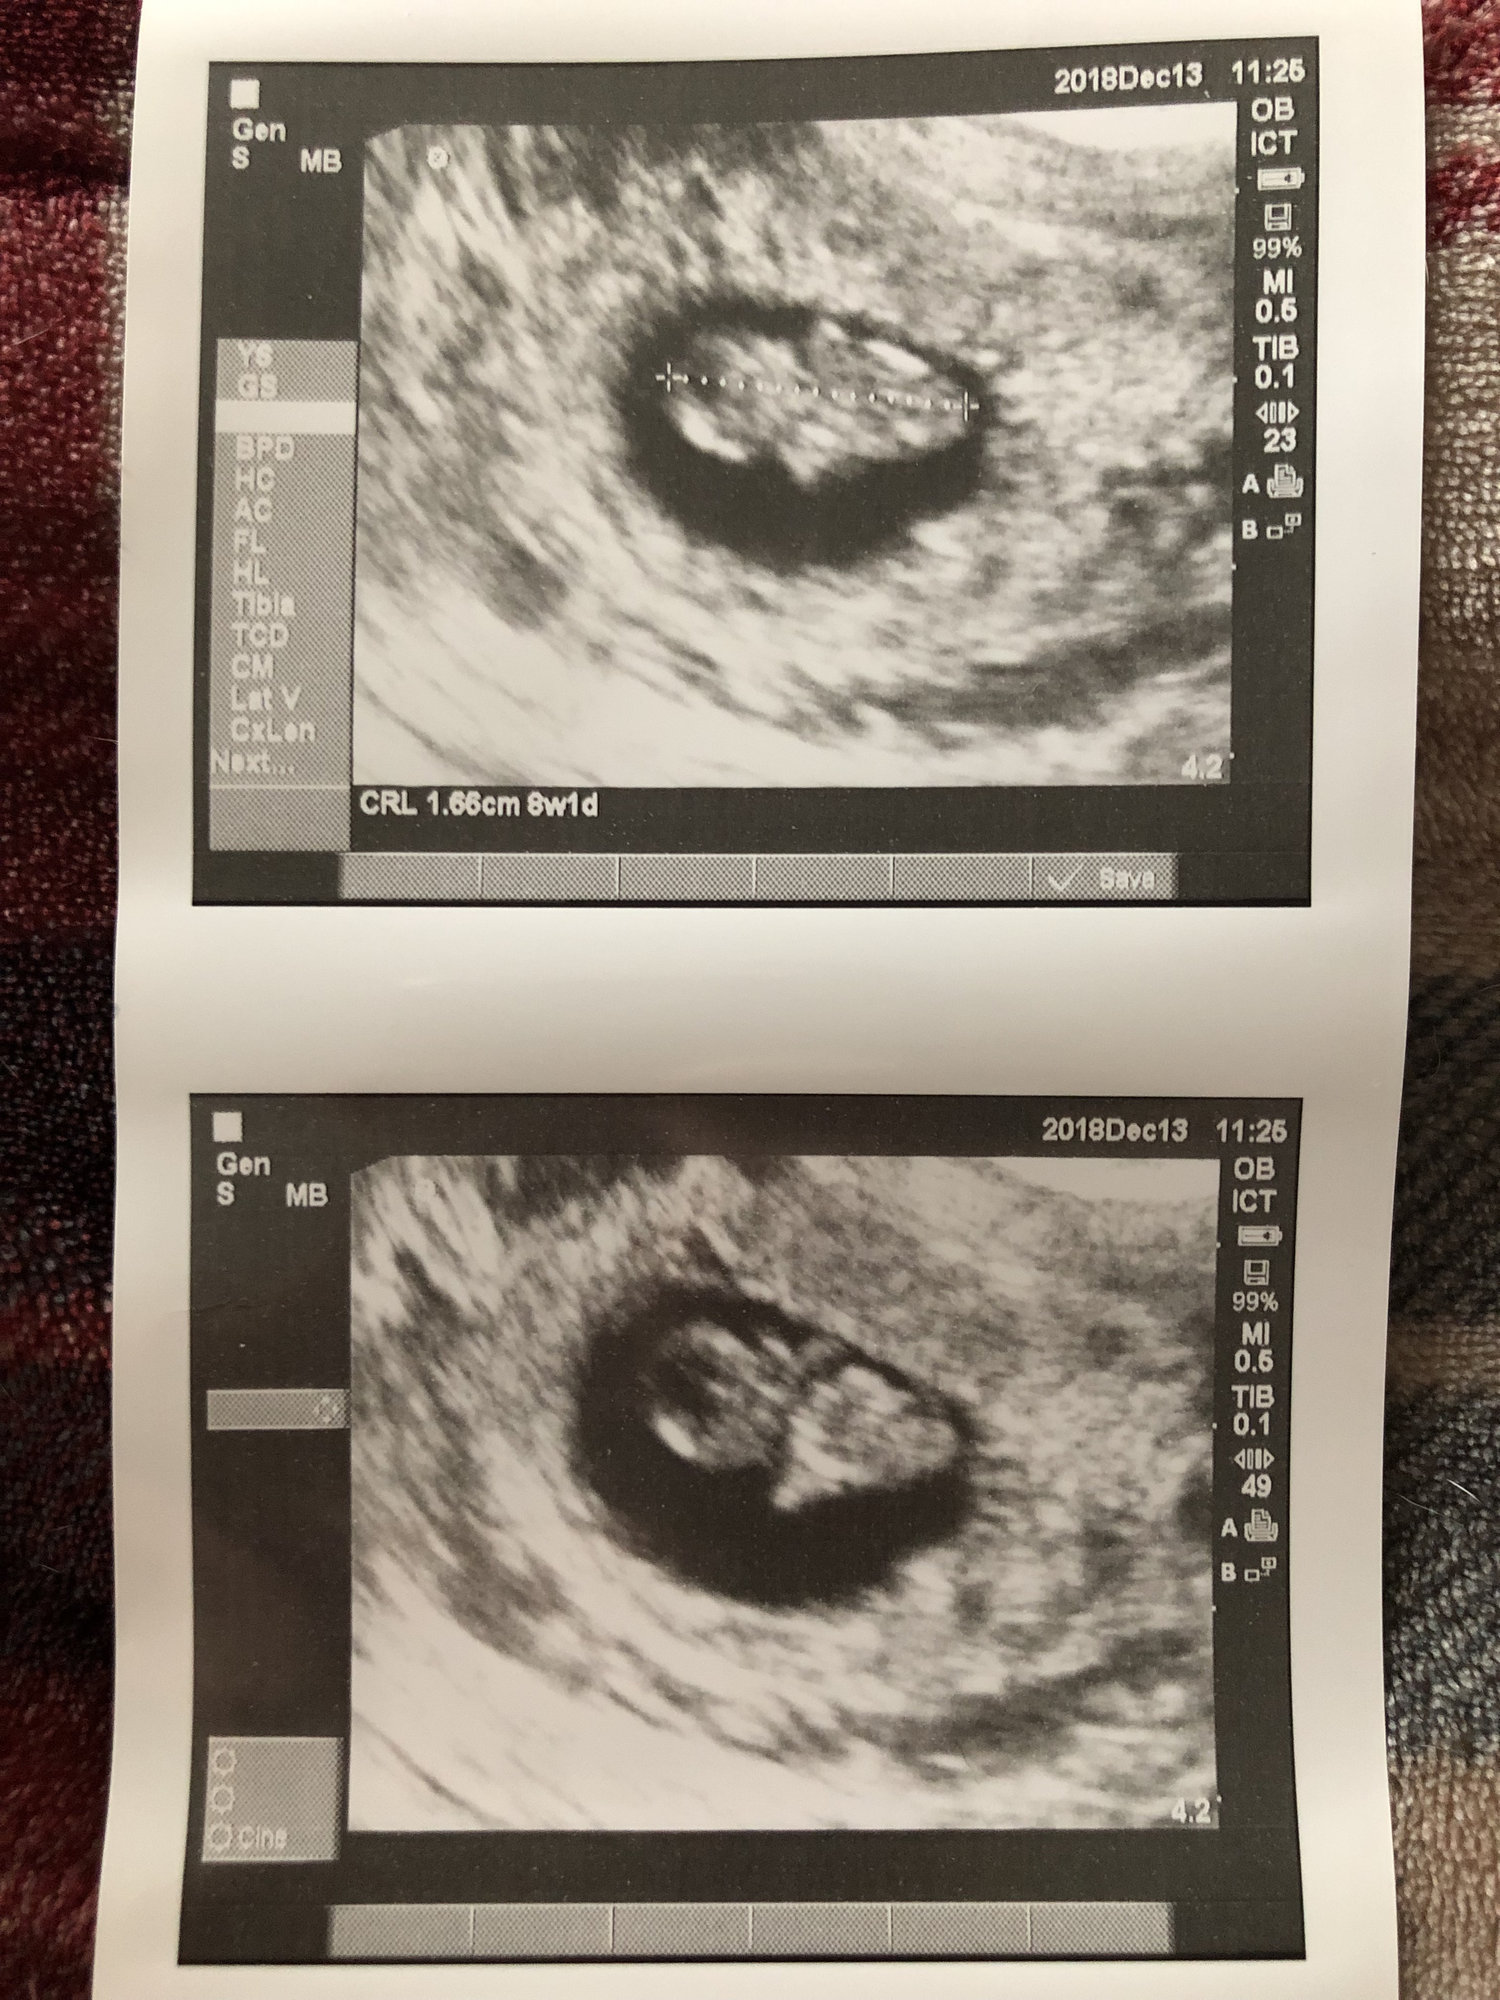

Second ultrasound! I’m 9 weeks today and baby is measuring 8wks 4 days. Within the margin so they’re keeping my 7/11 due date. Strong heartbeat at 178!

Went and saw baby again today, and learned that I am actually 10weeks1day not 9weeks4days. They are keeping my original due date since baby is growing. Next appointment will be with my OB to do the DNA testing